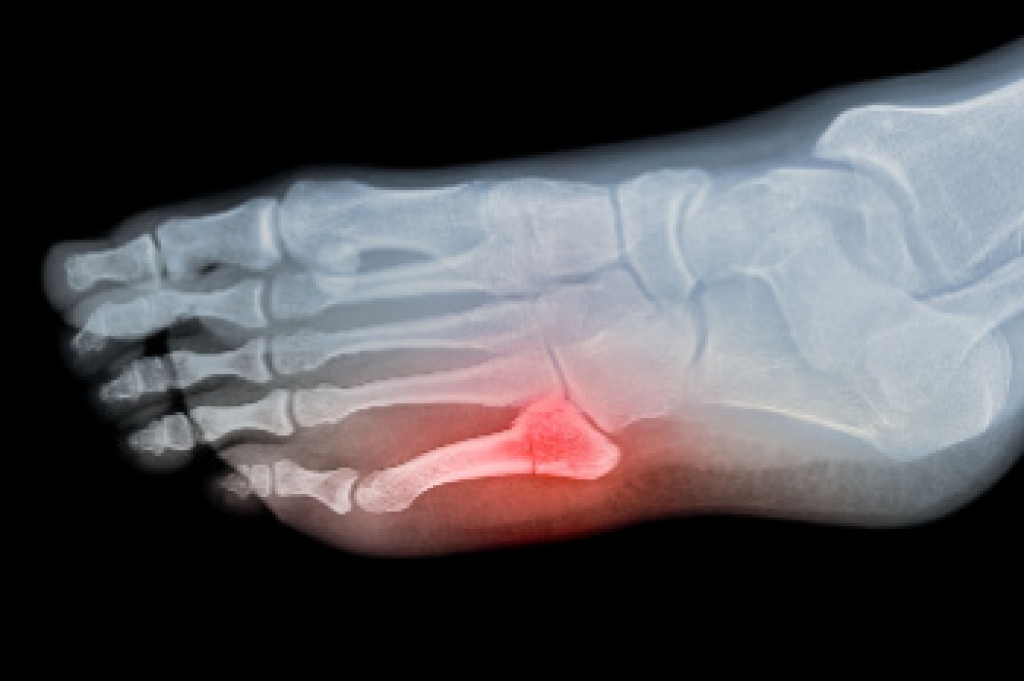

Broken Foot Causes, Symptoms, and Treatment

A broken foot is caused by one of the bones in the foot typically breaking when bended, crushed, or stretched beyond its natural capabilities. Usually the location of the fracture indicates how the break occurred, whether it was through an object, fall, or any other type of injury.

A broken foot can present with several clear symptoms, and it is vital to identify them for prompt treatment. One of the most telling signs is a sharp, severe pain that often worsens with movement or weight-bearing activities. A sensation of dislocated bones, where the foot feels misaligned or abnormal, is also common. Swelling and bruising typically develop rapidly around the affected area, indicating internal bleeding and inflammation. Visible deformities or an inability to move the foot or toes may also occur, in addition to a pronounced tenderness when touching the injured area. Treatment may include immobilization with a cast, use of crutches, and in severe cases, surgical intervention to realign the broken bones. If you feel you may have broken your foot, it is suggested that you consult a podiatrist who can accurately diagnose it and treat it accordingly.

Treatment for broken bones varies depending on the cause, severity and location. Some will require the use of splints, casts or crutches while others could even involve surgery to repair the broken bones. Personal care includes the use of ice and keeping the foot stabilized and elevated.